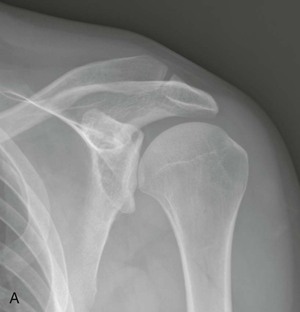

Optimal conventional radiographic views have been described for identifying these variations of the osseous outlet.71-74 The AP radiograph at a 30-degree caudal angle (Fig. 44-8) is helpful in visualizing the anterior aspect of the acromion and in detecting inferiorly directed enthesophytes.72 A modified transcapular lateral view obtained with 10 to 15 degrees of caudal angulation (the supraspinatus outlet view) helps further identify the anteroinferior aspect of the acromion.75 A high-riding humeral head with remodeling of the undersurface of the acromion and sclerosis of the greater tuberosity are conventional radiographic findings (Fig. 44-9) that are pathognomonic of a chronic rotator cuff tear. Although conventional arthrography, ultrasonography, and CT offer improved visualization of the rotator cuff relative to conventional radiography, they add little in the direct evaluation of the osseous outlet.

Conventional radiography plays only a limited role in the direct evaluation of the rotator cuff, although it is frequently the initial imaging study performed for patients with the clinical syndrome of impingement. Radiographs allow identification of associated pathologic change, especially of the osseous outlet and acromion. Conventional radiography findings associated with cuff pathology include the following2,100,101:

• A high-riding humeral head (<7 mm between the humeral head and the undersurface of the acromion) is associated with a chronic rotator cuff tear

• Scalloping and loss of normal acromion undersurface convexity (see Fig. 44-9)